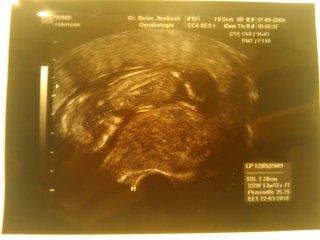

und nochmal zum KS.. also ich hatte meinen ersten sohn schon per KS entbinden muessen da mein MuMu nich aufging und er total straff war.. gestern meinte der arzt das ich vielleicht nochmal nen KS brauch.. aber ich WILL NICHT.. da das unser letztes kind ist will ich wenigstens eins normal entbinden.. ich lass es auf mich zukommen.. ich werd jetzt auch nicht fest mit nem KS rechnen..oder sogar einen planen..wenns los geht dann gehts los und dann kann man immer noch weiter gucken... das schaffen wir schon =p aber hier ist mal n bildchen von meiner kleinen bauchmaus.. sehr suess hat auch scho gestrampelt und getretten beim US.. jetzt nochmal 3 wochen warten und dann darf ich schon wieder zum doktor.. LG manu

Bild zu US bildchen von gestern! - Forum für März - Mamis

Total süßes Bild... wie groß ist "es"? lg Manu